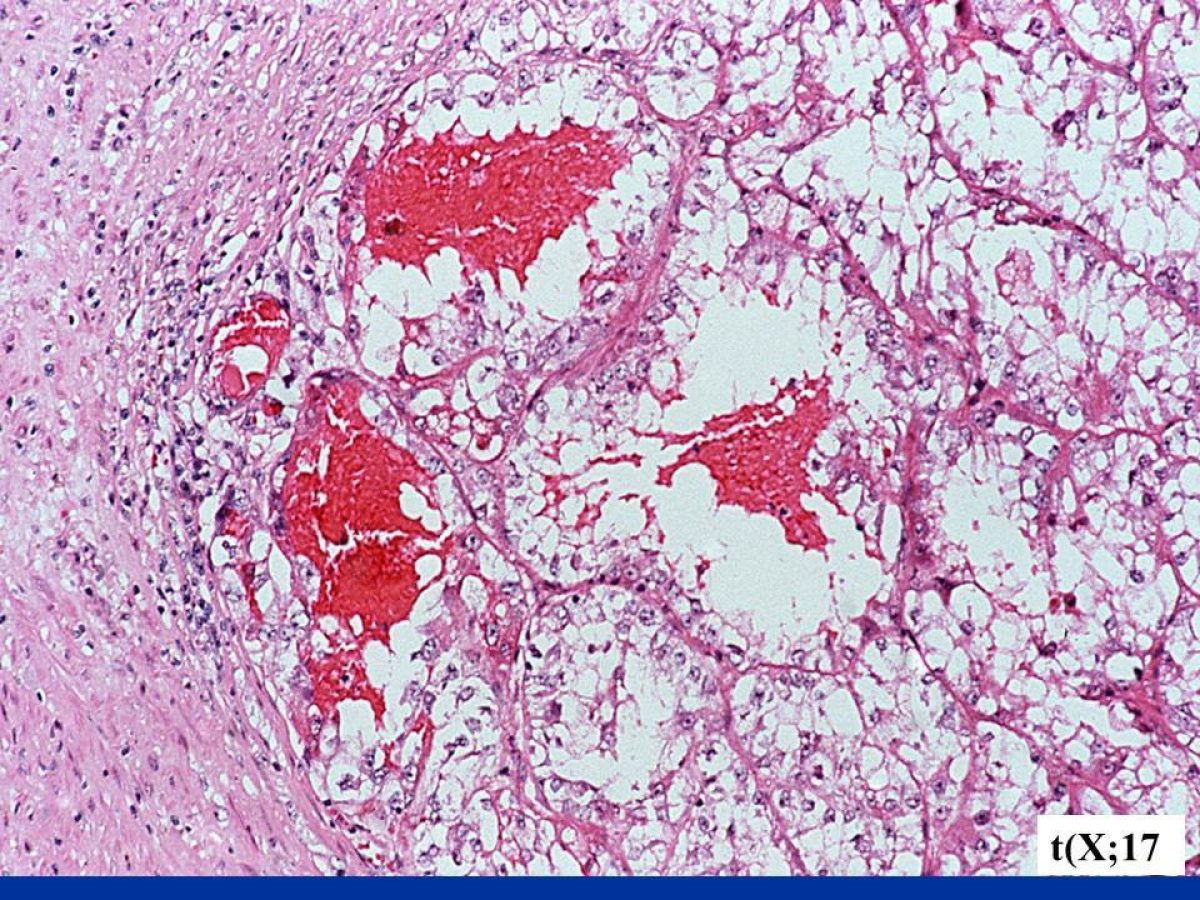

These pathology images are examples of what Translocation Renal Cell Carcinomas look like under the microscope.